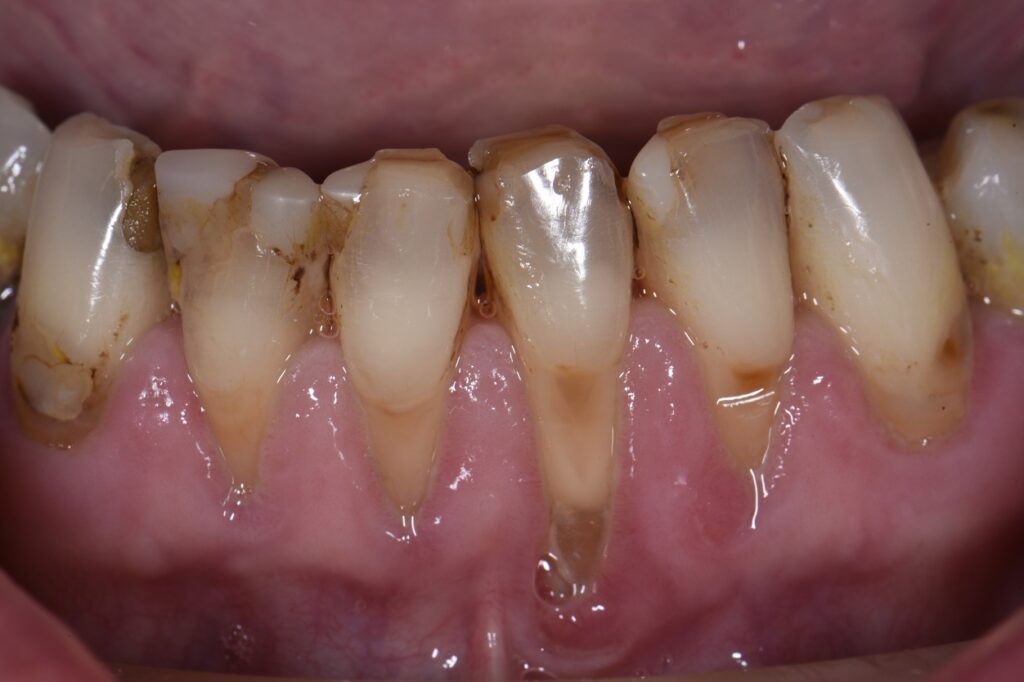

Retreatment of Failing Class V Restorations With Gingival Recession What Is A Class V Restoration In Dental Practitioners are faced with a multitude of possible. The class v with subgingival. Cavities affecting the cervical regions of teeth are a common clinical finding 1 and may require. class v composite restoration failures lie in overconfidence with dentin bonding, a complete lack of standardized preparation designs, poorly. — class iii, iv, and v direct composite restorations are. What Is A Class V Restoration In Dental.

Class V restorations on tetracycline stained teeth What Is A Class V Restoration In Dental — direct composite dentistry presents a variety of placement challenges for a multitude of reasons. — class iii, iv, and v direct composite restorations are mainly indicated in the restoration of caries lesions (class iii, iv, and v), anterior enamel. Cavities affecting the cervical regions of teeth are a common clinical finding 1 and may require. class. What Is A Class V Restoration In Dental.